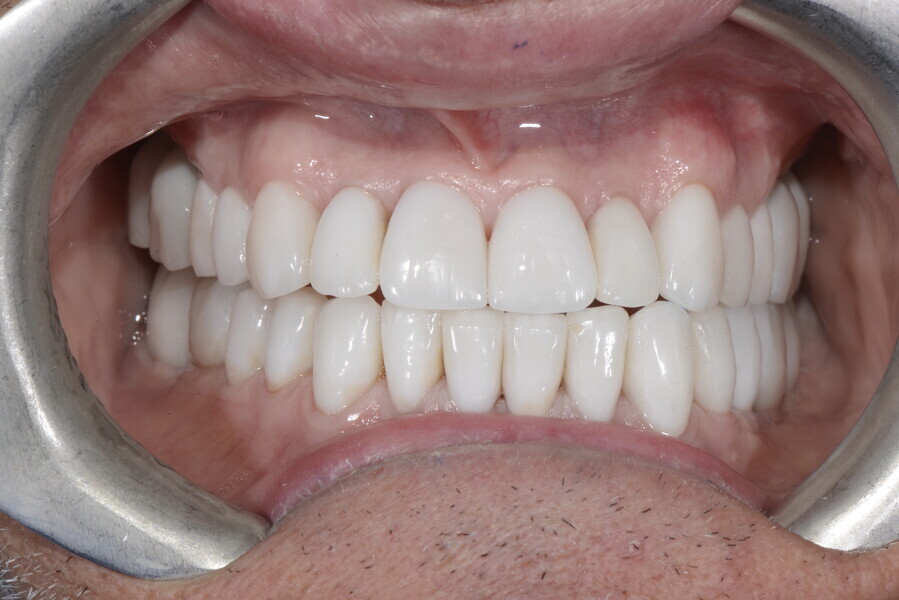

After the first phase of aligner treatment, we had achieved better inter-arch coherence, better maxillary arch expansion, and some space for improving the anterior tooth proportions restoratively (Fig. 19). We then temporarily restored the anterior teeth directly with composite, closing the spaces, improving the tooth proportions and further increasing the maxillary arch expansion (Fig. 20). We used restorative arch expansion to reduce the orthodontic destabilisation of the teeth to achieve the correct inter-arch coherence and retain the teeth in the cortical bone.38 A refinement aligner phase was undertaken to improve the final alignment of the gingival zenith and to improve the inter-arch coherence (Fig. 21). The periods of the first orthodontic phase and of the refinement were used to augment the mandibular and maxillary bone and to place the implants (Fig. 22). At the end of the orthodontic treatment, the case was finalised with ceramic veneers in the anterior area and temporary restorations on the implants in the posterior area (Figs. 23–26).

The provisional phase of about four months was important to allow the peri-implant tissue to mature and to teach the patient to chew correctly with chewing gum, cotton rolls and silicone masticatory sticks. This is fundamental training for the patient to achieve the correct alternating unilateral masticatory cycle needed to obtain the ideal rehabilitation of the masticatory system. We wanted the patient to achieve ideal masticatory and swallowing function. After sufficient rehabilitation time, we finalised the case with posterior zirconia crowns screwed on to the implants (Fig. 27).26

Our ideal final rehabilitation goals were:

• posterior stability;

• inter-arch coherence and U-shaped arches;

• anterior freedom during mastication;

• minimum disclusion vertical dimension;

• alternating unilateral masticatory cycle;

• physiological swallowing and high tongue posture against the palate; and

• mandibular disclusion advancing the mandible freely.

For maintenance purposes, after prosthetic finalisation, the patient was to carry on with the Froggymouth therapy and to use the Ri.P.A.Ra. for physiotherapeutic exercises and mastication training (Fig. 28). It was strongly recommended that the patient wear a mandibular occlusal splint during sleep. This occlusal splint was designed with disclusion guides to advance the mandible and ensure balanced contralateral support (Fig. 29).11, 39 We achieved an aesthetic appearance with adequate inter-arch coherence and a better cephalometric result (Figs. 30 & 31).